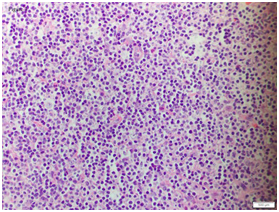

A series of investigations were soon conducted. An ultrasound B-scan (brightness scan) on his left eye showed absence of clinical sign of posterior scleritis (T- sign). Computed tomography scan of orbits and paranasal sinuses showed left proptosis and marked swelling of all the extra-ocular muscles in the left eye. There was no mass lesion seen. Blood tests were not conclusive but revealed high erythrocyte sedimentation rate (ESR) at 80 mm/hr and raised white cell count at 11.2 x 103/L with lymphocytosis at 51.5%. Thyroid function tests, haemoglobin and platelet levels were normal. The patient subsequently underwent left eye’s tenon capsule and superior rectus muscle biopsy for histological diagnosis. The superior rectus muscle histology displayed small B-cell lymphocytic infiltrate with irregular nuclei, indistinct nucleoli and scattered centroblasts (Figure 2; eye muscle histology). Immunohistochemistry showed a predominant CD20+B cell population in the biopsy sample. The tenon’s capsule biopsy showed perivascular lymphocytic

Figure 2 Eye muscle biopsy: Fibro-collagenous tissue with predominant atypical small ‘B’ cell lymphoid infiltrates and aggregates (Hematoxylin and Eosin, 40X).